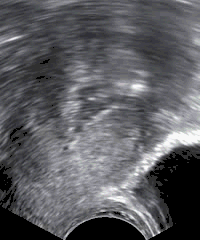

| Sonohysterography performed because of postmenopausal bleeding. In serial images, polyps would be less mobile than the freely moving debris seen within the uterine cavity in the image. | |